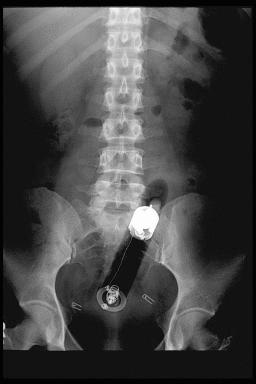

Click to enlarge.....